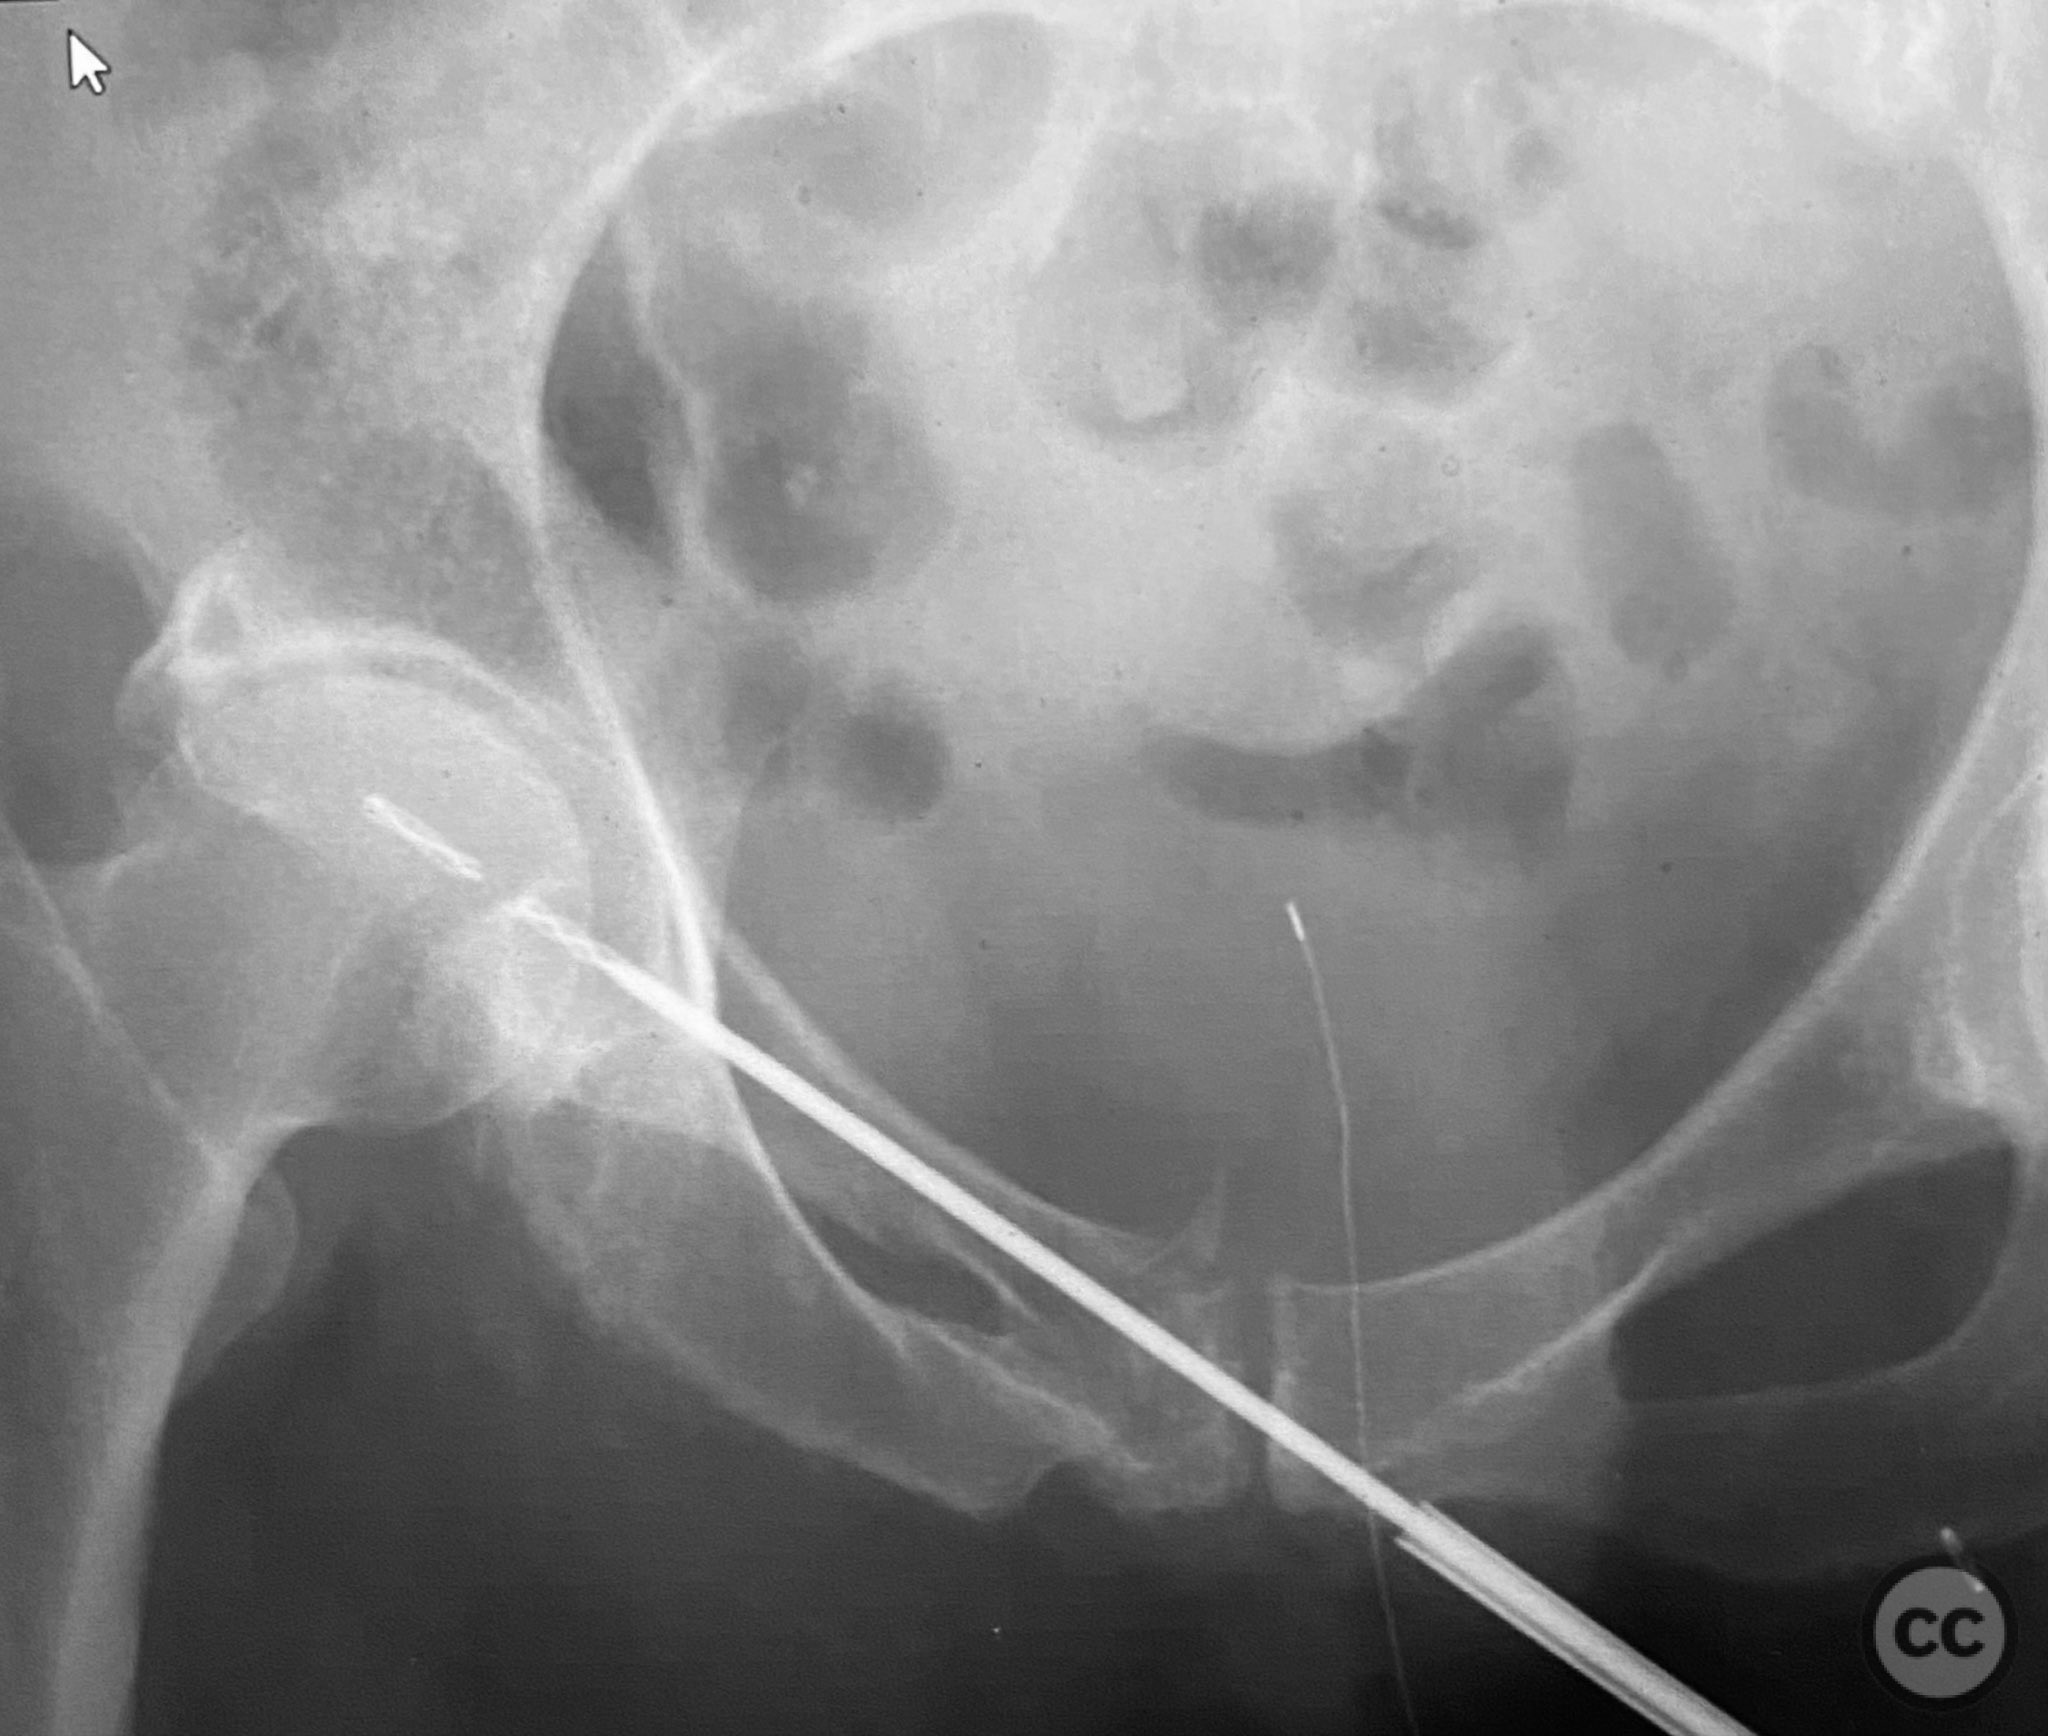

Intraoperatively, a 3.5mm drill was used through a protective sleeve to initiate the screw pathway across the superior pubic ramus. Due to poor bone quality, a 2.5mm drill was subsequently employed; however, resistance was encountered as the drill tip engaged the dense cortical apex of the anterior acetabular wall. The drill became lodged in this region. To avoid drill breakage, manual extraction using pliers was considered; however, the surgeon elected to carefully deflect and advance the drill manually, successfully completing the pathway. Screw length was measured directly from the embedded drill tip. A 4.5mm cortical screw was then inserted trans-symphyseally along the prepared medullary canal, achieving stabilization of the unstable ramus fracture. Postoperative CT confirmed appropriate screw trajectory and demonstrated the dense cortical bone at the anterior acetabular wall where the drill tip had engaged.